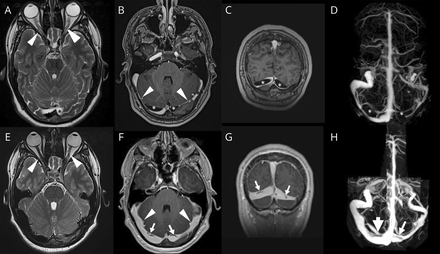

一个16岁的男孩与周期性瞬态视觉丧失了双边视神经乳头水肿。MRI显示巨大蛛网膜颗粒(GAG)横向鼻窦和颅内高血压的迹象(图)。CSF开启压力是420毫米H2o .减少血液的腰椎穿刺后,呕吐的大小减少和窦腔狭窄解决(图)。蛛网膜颗粒(AG)脑脊液椎间盘硬脑(脊)膜通过鼻窦。1CSF去除导致他们回归以来,呕吐可能颅内高血压的结果。我们支持Krisch理论,认为AG)是一个缓冲的CSF室而不是一个网站脑脊液吸收。2

图

减少血液的腰椎穿刺后脑脊液和血液间变化

轴向t2加权图像显示视神经曲折(箭头)。轴向(B)和额叶(C) postcontrast t1加权成像和磁共振造影术(D)揭示巨大蛛网膜颗粒(GAG)(星号)和窦腔狭窄(箭头,B)。五天后腰椎穿刺,视神经曲折(箭头,E),呕吐(箭头,F-H)和窦腔狭窄(箭头,F)消失。